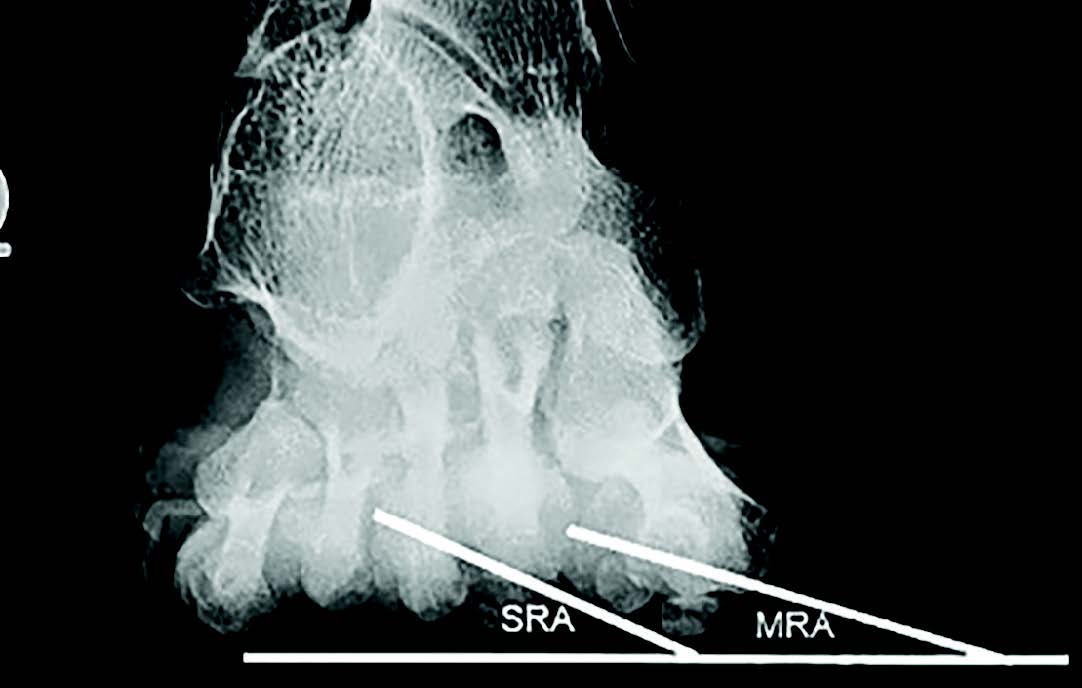

Saltzman and colleagues used the plantar axial radiograph to measure axial rotation of the head of the first metatarsal, introducing the metatarsal pronation angle (MPA).61 (see figure 4) These researchers found that patients with HAV deformity had a mean pronation rotation of 5.7 degrees while healthy control subjects had 1.6 degrees; however, the wide range of rotation measured in both groups negated the statistical significance of the differences.